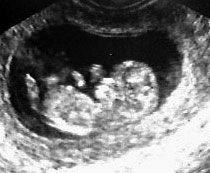

После первого укола папаверина, мазня прекратилась, через пару деньков с уколами и таблетками у меня перестал болеть животик и я пошла на поправку....через неделю мне зделали УЗИ

, где сказали, что мой малыш живой и здоровенький, чему было подтверждение, его бьющееся сердечко, которое мне показали, но....гадкий тонус все не проходил никак...и меня оставили лечится дальше...вся моя попка была синяя от уколов, но мне было все равно, я готова была терпеть все только бы с малышом было все в полном порядке!

И вот спустя 15 дней нас выписали!!!! Сегодня перед выпиской у нас было контрольное УЗИ, срок соответствует, развиваемся просто отлично, тонус совершенно прошол и у нас все великолепно!!!!

И есче...мой малыш мне помахал рученкой, я там чуть не разрыдалась от счастья!!!

Вот мы какие теперь....)))))